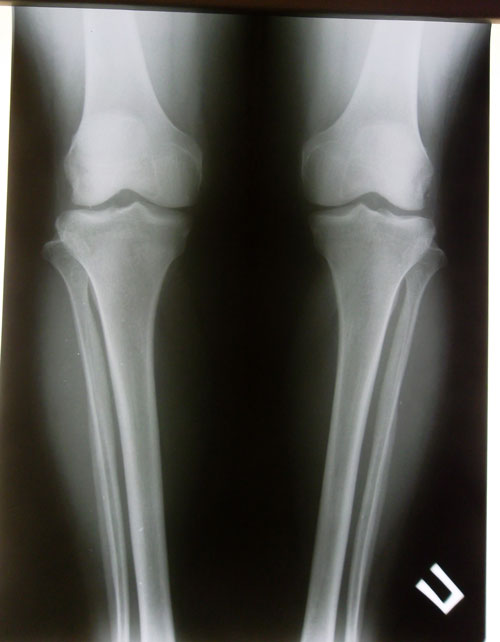

Дата операции 06.12.2013г.

Дата снятия аппаратов 26.02.2014г.

Срок лечения 80 дней.

Натальины ножки через 2 месяца после снятия аппаратов. На работе!